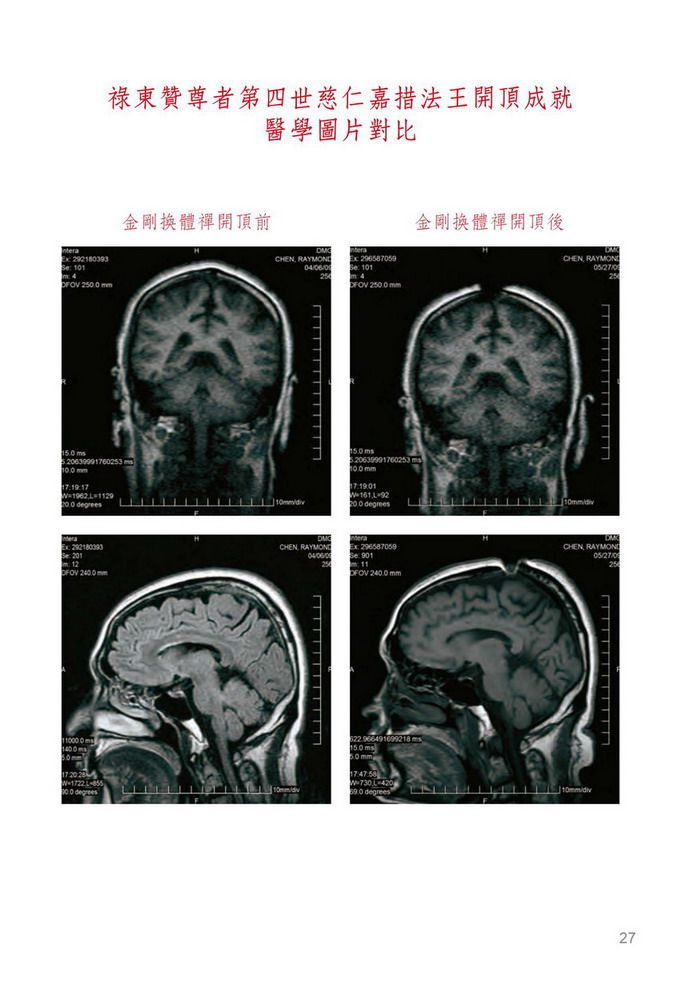

今天既然說到開頂的事也明告世上修行之人,你千萬不要相信插上吉祥草這就是證聖的境界啦,真正證聖不是凡夫的事,首先看一下那自吹開頂的人他真的開頂了嗎?有證據嗎?這可不是插上一支吉祥草或用脫髮水脫掉一縷頭髮就證明開了頂的,你們要弄清楚,那吉祥草硬如竹籤,哪一個人的頭皮都能隨處插上。哪怕吃下幾粒具生命力能在弟子自己手中活躍的金剛丸,這頂也開不了的,那一定要服上一口真正的佛降甘露作為法緣基礎,而且要灌金剛換體禪的境行之頂才能打開大樂頂門,這非同小可,正如妙空法師體悟說:「驚天動地啊!」真正開頂可不這麼簡單啊!學佛人要知道,但凡學佛成就或往升者必須要開了頂才行,而且任何佛法只要修成就,就會開頂,但都是中陰身成就的,如果頂都沒有開,神識又從什麼地方出沒肉體呢?只能由六道轉輪處出走神識,其實不具《解脫大手印》灌頂境行的人是不行的,就是破阿法開了頂,最多也只有一毫米寬,而且神識一當出體後就回不去了,所以只能中陰往升淨土,亦稱為中陰身最好的救度法。只要是受了《解脫大手印》勝義內密灌頂境行法,其功德力大於常規佛法萬倍之多,神識出體後又能返回,十分自由,這功力之強大,不是一句空話,而是實語、如語、無妄語。比如能讓受灌者在一個時辰之內證到虹身境界,但是修大圓滿需經十二年之久,乃達成就者少之;又如金剛換體禪,也是只需一個時辰開大樂輪門之頂,用以現代科學檢視證實頭頂開一指到二指寬的空口不等,乃至其洞深入腦底,達透五輪,神識出入自由,這在常規佛法是沒有的功德道力。要注意的是已經修《解脫大手印》的人,你除了只能加修護法之外,其他任何佛法皆不可以混入修持;但是凡沒有領受到境行修持的人,可以只修《解脫大手印》前行和正行,也可以不修「福壽財富成就法」而加入你曾經修過的本尊正行,溶入在《解脫大手印》前行、正行中修持。但切記不可以與你原有的前行混修,如果你認為法本太長,你可只選《解脫大手印》前行、正行加入你原有的本尊心咒和形相觀修就很圓滿了,只要是加入《解脫大手印》前行、正行、結行而修,就這麼簡單的修持,其功德力也是比常規佛法的成就要大十幾倍的。比如開頂成就解脫就是鐵證,我看到開初仁波且和妙空法師是真開了頂的,而不是那虛名的所謂開頂插吉祥草,他們是跟我一樣受《解脫大手印》金剛換體禪境行灌頂開的頂。在灌頂當時,頭頂肉與骨的表顯則是完好無異樣變化,卻能開能關,在醫學的照片檢視上清清楚楚就是開頂了,並且照到了靈識出體的剎那氣相體,確實證明肉與骨頭、腦膜、腦髓都不見了一到二指寬,其中一位出現螺旋狀洞口,一條線一直深入大腦中心,另一位則洞有雞蛋大小,直入腦底,他們二位才是真金大聖德、大王臣啊!無論什麼人所講空洞的理論都是代表不了實際成果的,所以千萬不要迷信那些說假話空洞理論派的假聖德。有的人借用他的上師是名門正聖的旗號,稱自己是正宗法承人,但是要清楚往往一位大德往升了以後,他門下的弟子們都會爭相爭奪繼承他的法脈,就算你真正把他的法脈完全繼承了,你所修的那些佛法跟《解脫大手印》比起來也是天地之差啊!比如有兩個小時成虹身的法嗎?有一個時辰金剛換體禪開頂二指寬,神識出沒自如嗎?根本就找不到,所以我說天地之差。